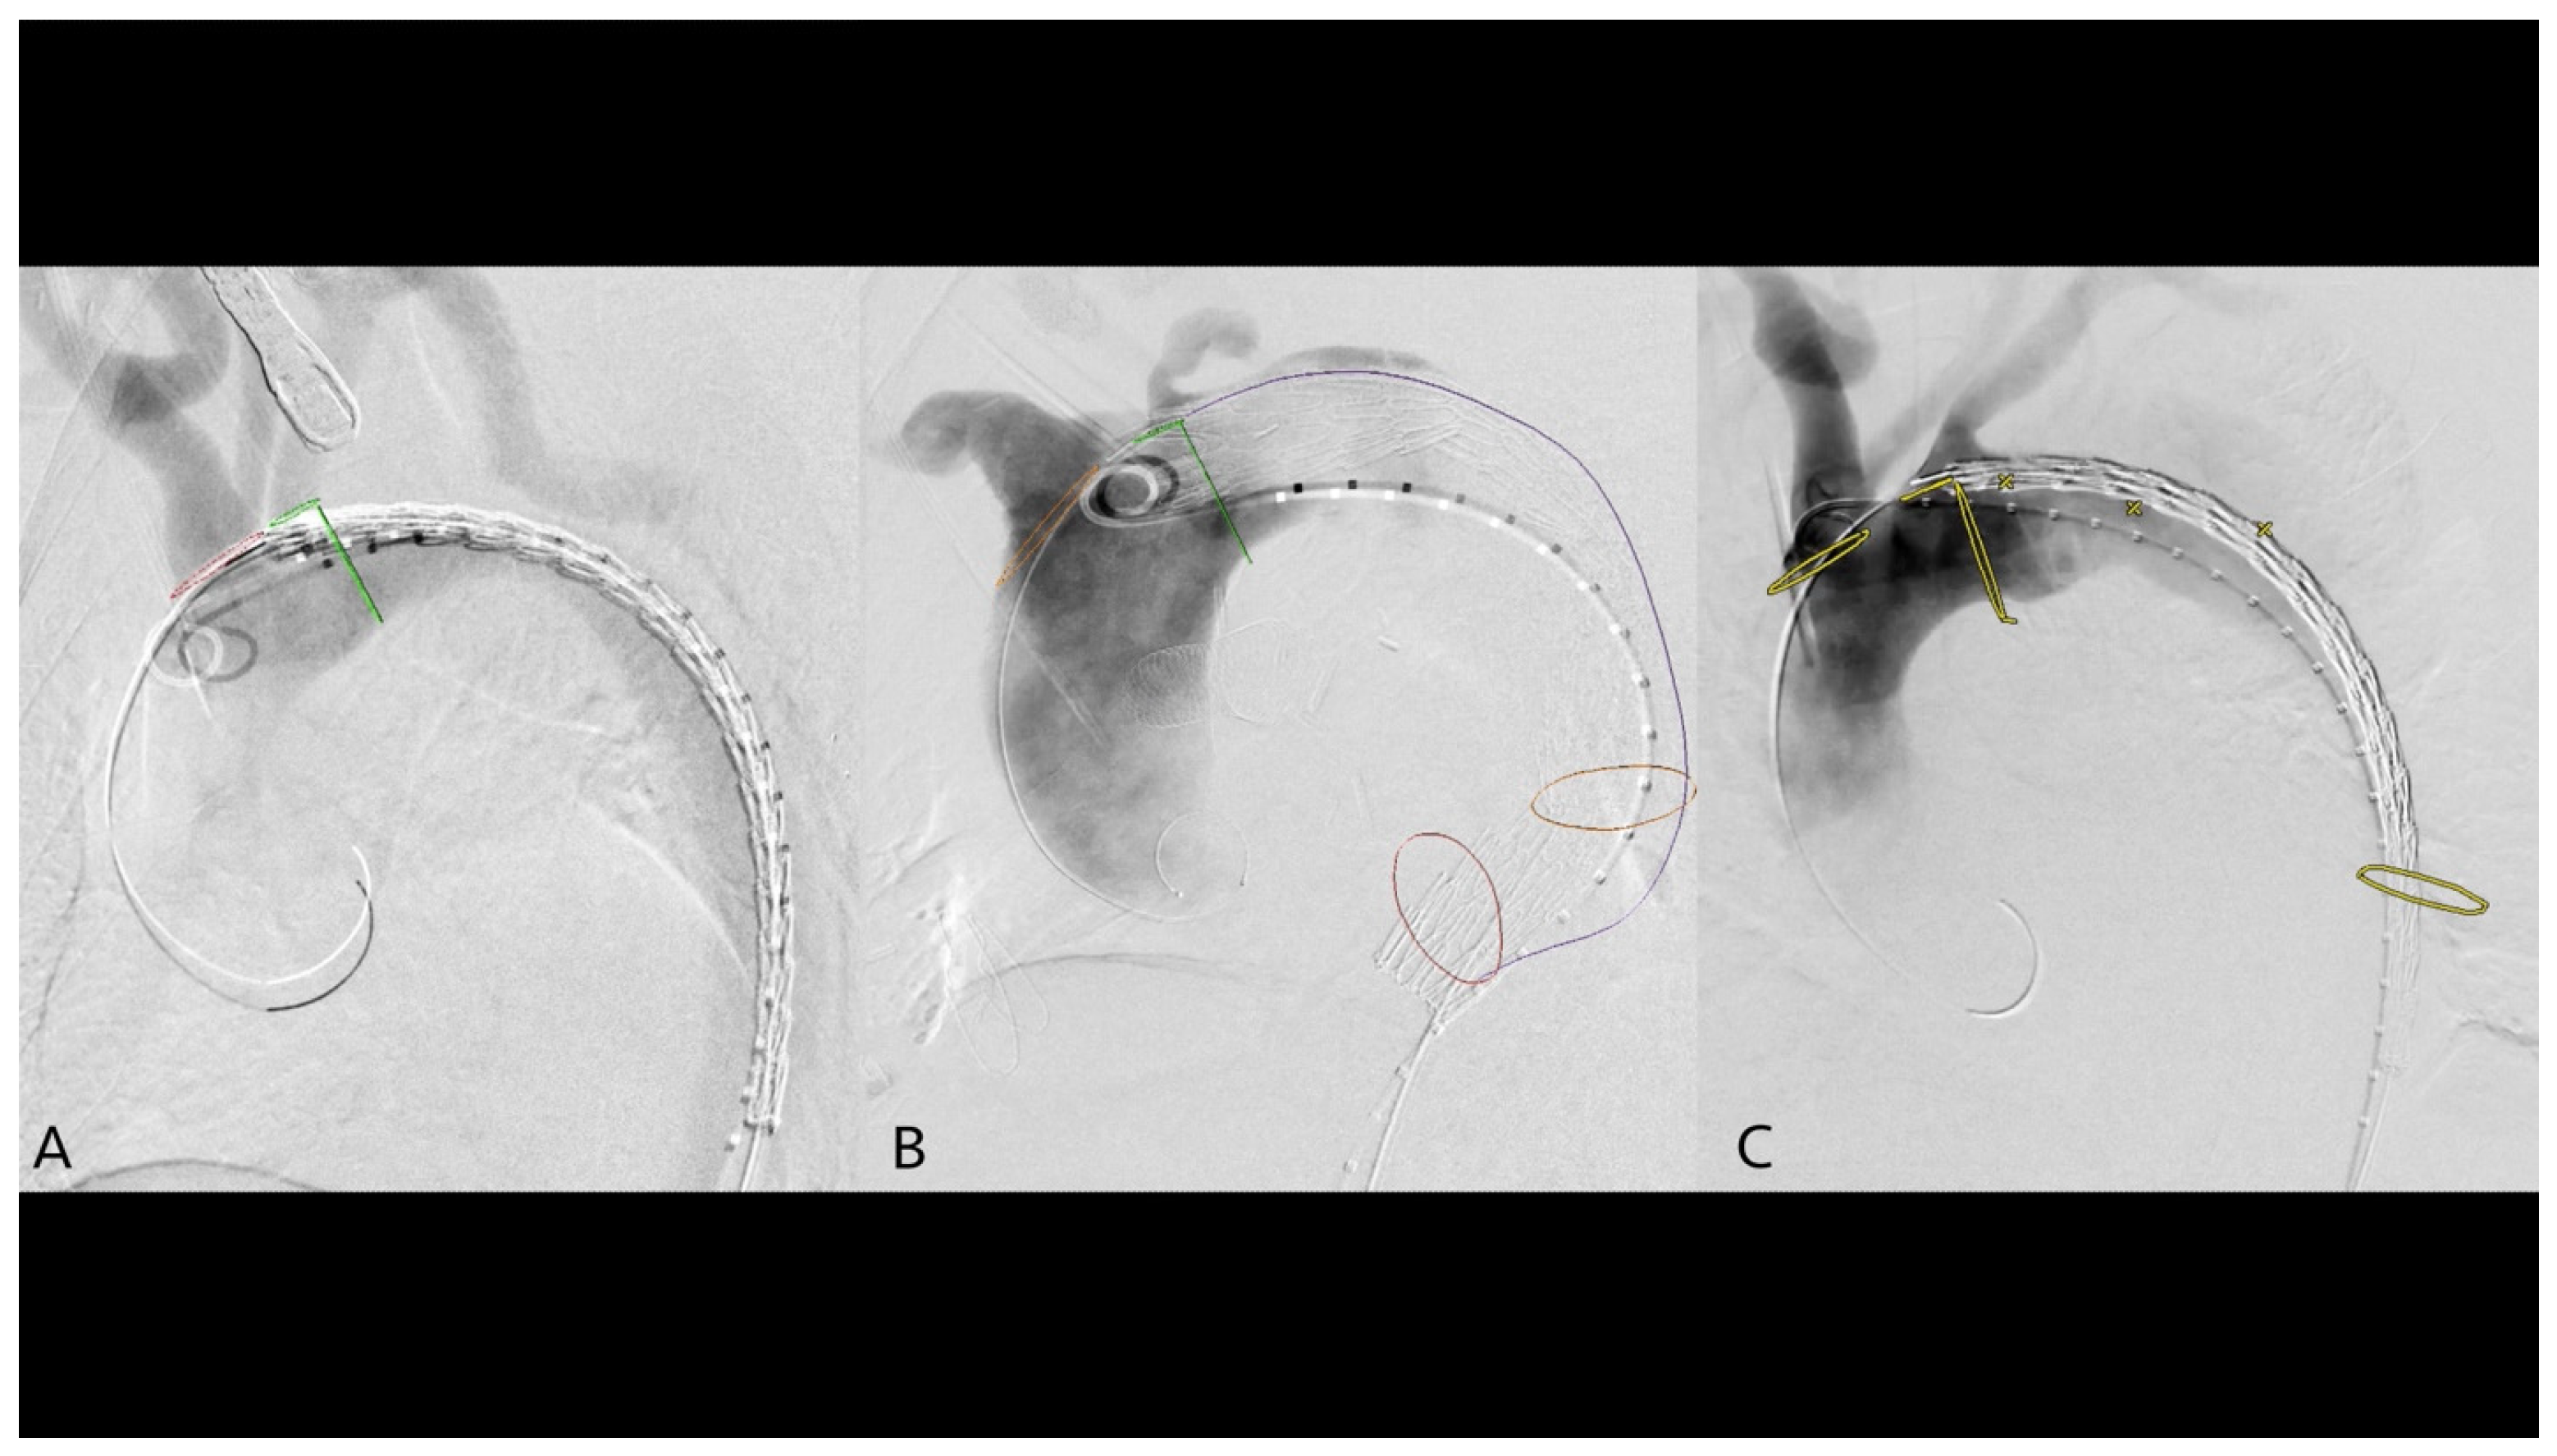

2.4. 2D3D Fusion Technique

2.5. 3D3D Fusion Technique